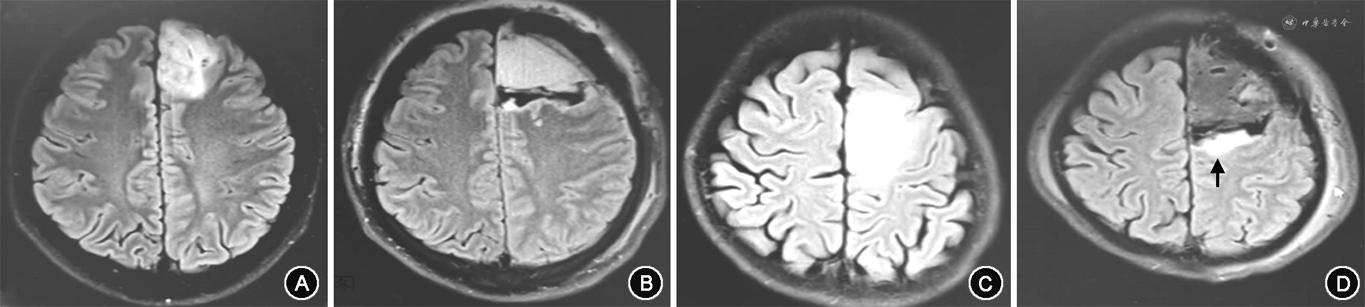

2. 方法:详细收集每例患者的一般资料、癫痫发作史、肿瘤部位、肿瘤侧别、肿瘤体积、瘤周水肿、分子病理类型、放化疗病史及肿瘤切除程度。切除程度根据术后72 h复查磁共振MRI Flair序列判定(图1):Flair影像上完全切除为肿瘤全切除,切除90%~99%为次全切除。术后癫痫疗效按照Engel分级进行分类,Engel Ⅰ级(完全没有癫痫发作)为癫痫预后良好组。EngelⅡ~Ⅳ级(偶尔癫痫发作,较术前明显好转,较术前无明显好转)为癫痫预后不良组。本研究符合《赫尔辛基宣言》对伦理的要求,知情同意豁免。